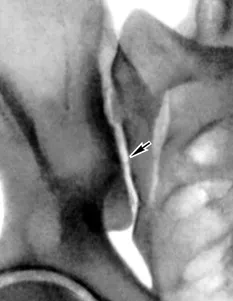

Схематическое изображение лечебно-диагностического введения смеси лекарственных препаратов в крестцово-подвздошное сочленение и рентген-контроль с контрастом.